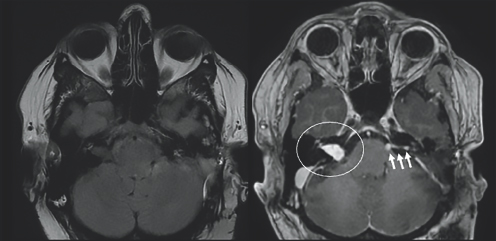

(Left) Dark gray colored structures are contained within a light gray outline. (Right) A white colored blob on the left side of the image is highlighted by a white circle. There is a white horizontal blob on the right side of the figure highlighted by three small white arrows. These blobs are located just above two conjoined gray spherical structures. All structures are enclosed by a gray outline.

FIGURE 8.1 Axial images before (left) and after (right) injection of IV contrast demonstrate enhancing mass in the right internal auditory canal that appears bright after being injected with IV contrast (white circle), consistent with schwannoma. Post-surgical changes from schwannoma resection with persistent enhancement within the left cerebellar pontine angle cistern that appears bright after being injected with IV contrast (white arrows), consistent with residual tumor.